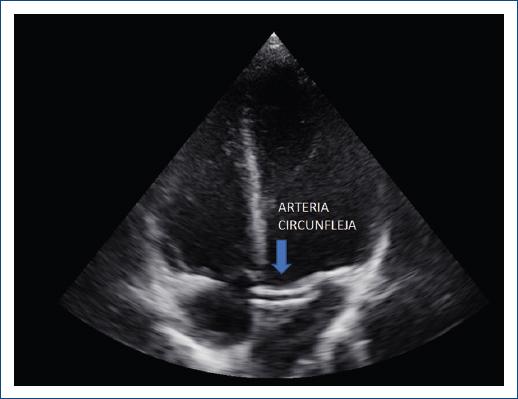

El ETT es la técnica de imagen inicial para la sospecha de esta anomalía. Por ello las arterias coronarias fueron evaluadas desde las vistas ecocardiográficas convencionales3,4 incluyendo la vista paraesternal eje largo (nacimiento de la ACD del seno, unión sinotubular o nacimiento alto desde la aorta ascendente), vista paraesternal eje corto con rotación horaria del transductor para visualizar la división del tronco de la ACI en la ADA y ACX y rotación antihoraria para identificar el trayecto de la ACD. El Doppler color permite la identificación del flujo coronario, pero dado que este tiene baja velocidad el límite Nyquist utilizado debe ser de 20-40 cm/s. Adicionalmente, nuestra estrategia de pesquisa incluyó un barrido minucioso anteroposterior entre 4 y 5 cámaras apical donde detectamos la ACA cruzando el tracto de salida del ventrículo izquierdo (VI) (Fig. 1) previamente considerado por otros autores como Bianco et al.5.

Figura 1 Barrido ecocardiográfico en vista de cuatro cámaras apical en sentido antero-posterior y postero-anterior observando trayecto coronario anómalo cruzando el tracto de salida de ventrículo izquierdo.